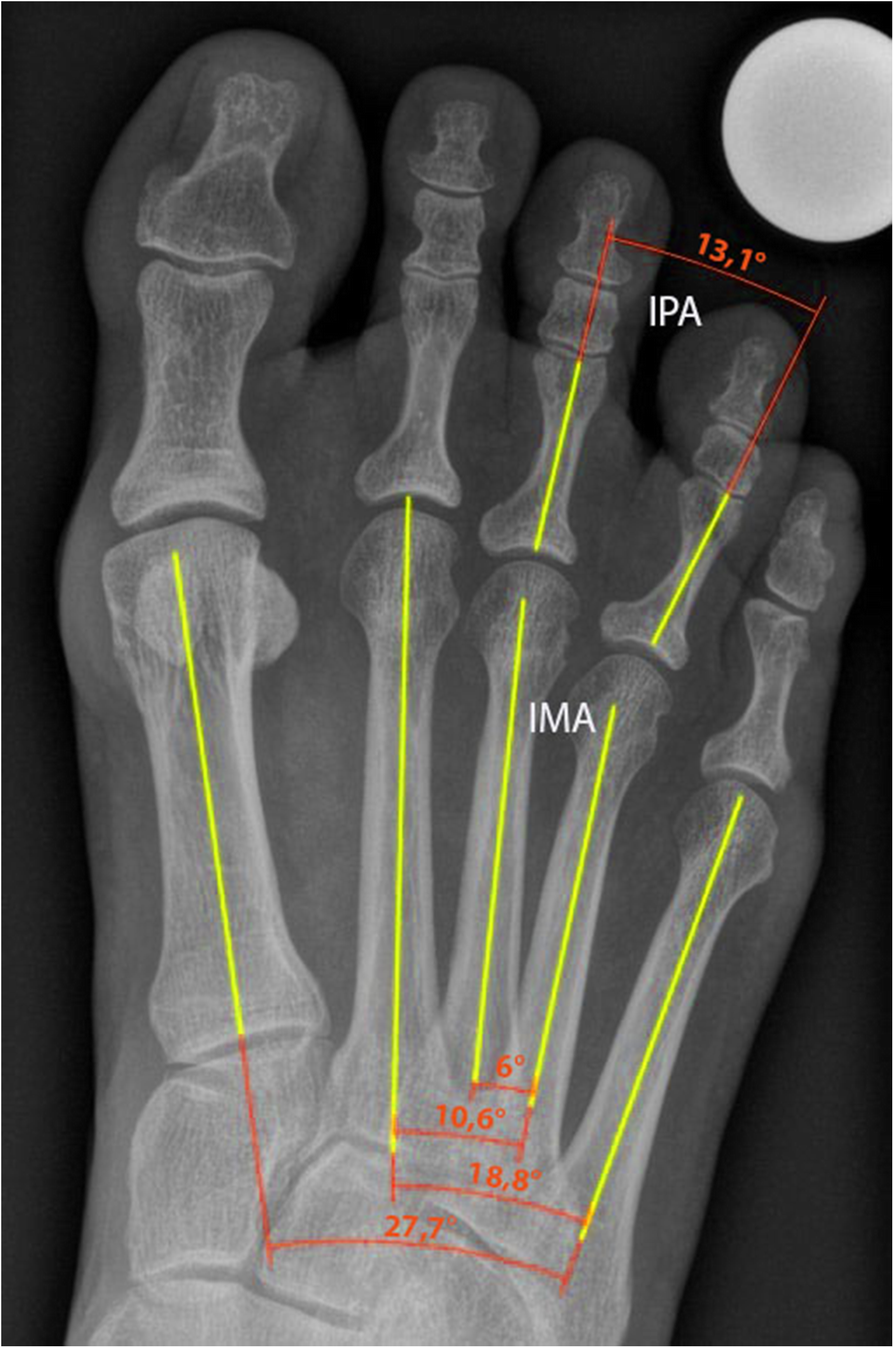

Radiological measurements

Fig. 1

Radiological measurements. IPA = Interphalangeal angle; IMA = Intermetatarsal angle